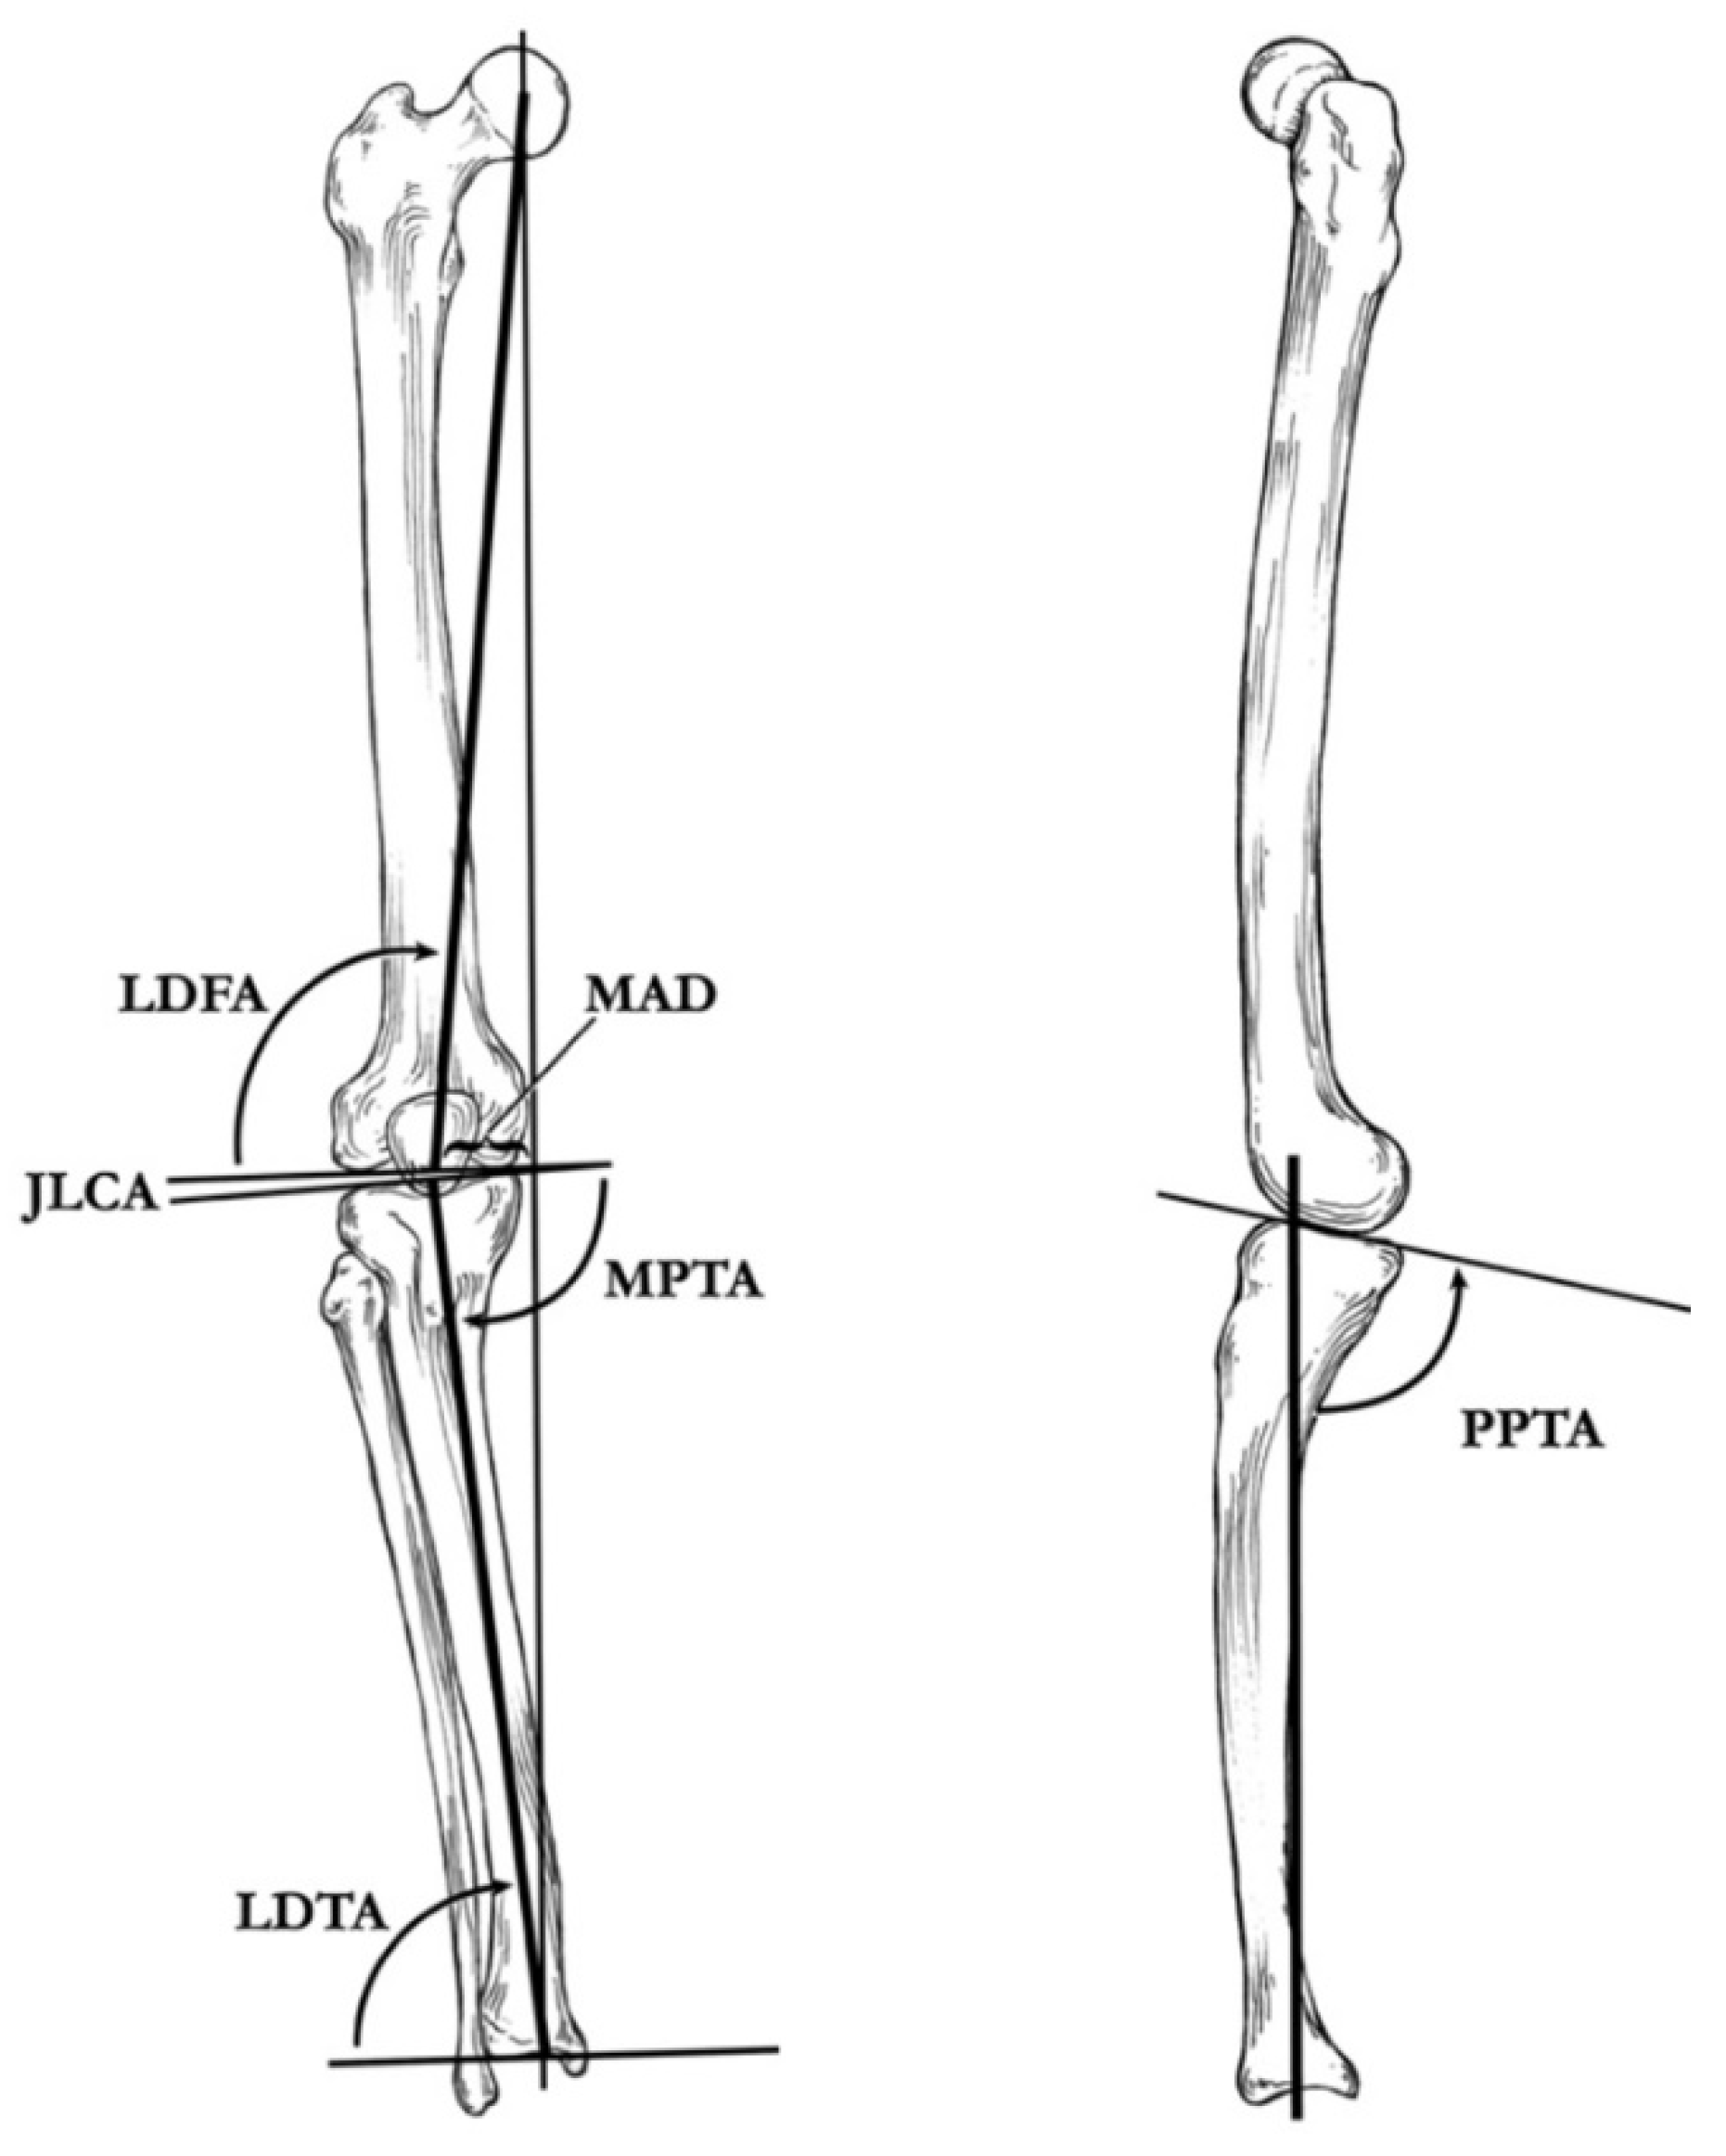

4. Radiographic Imaging

5. Radiographic Analysis